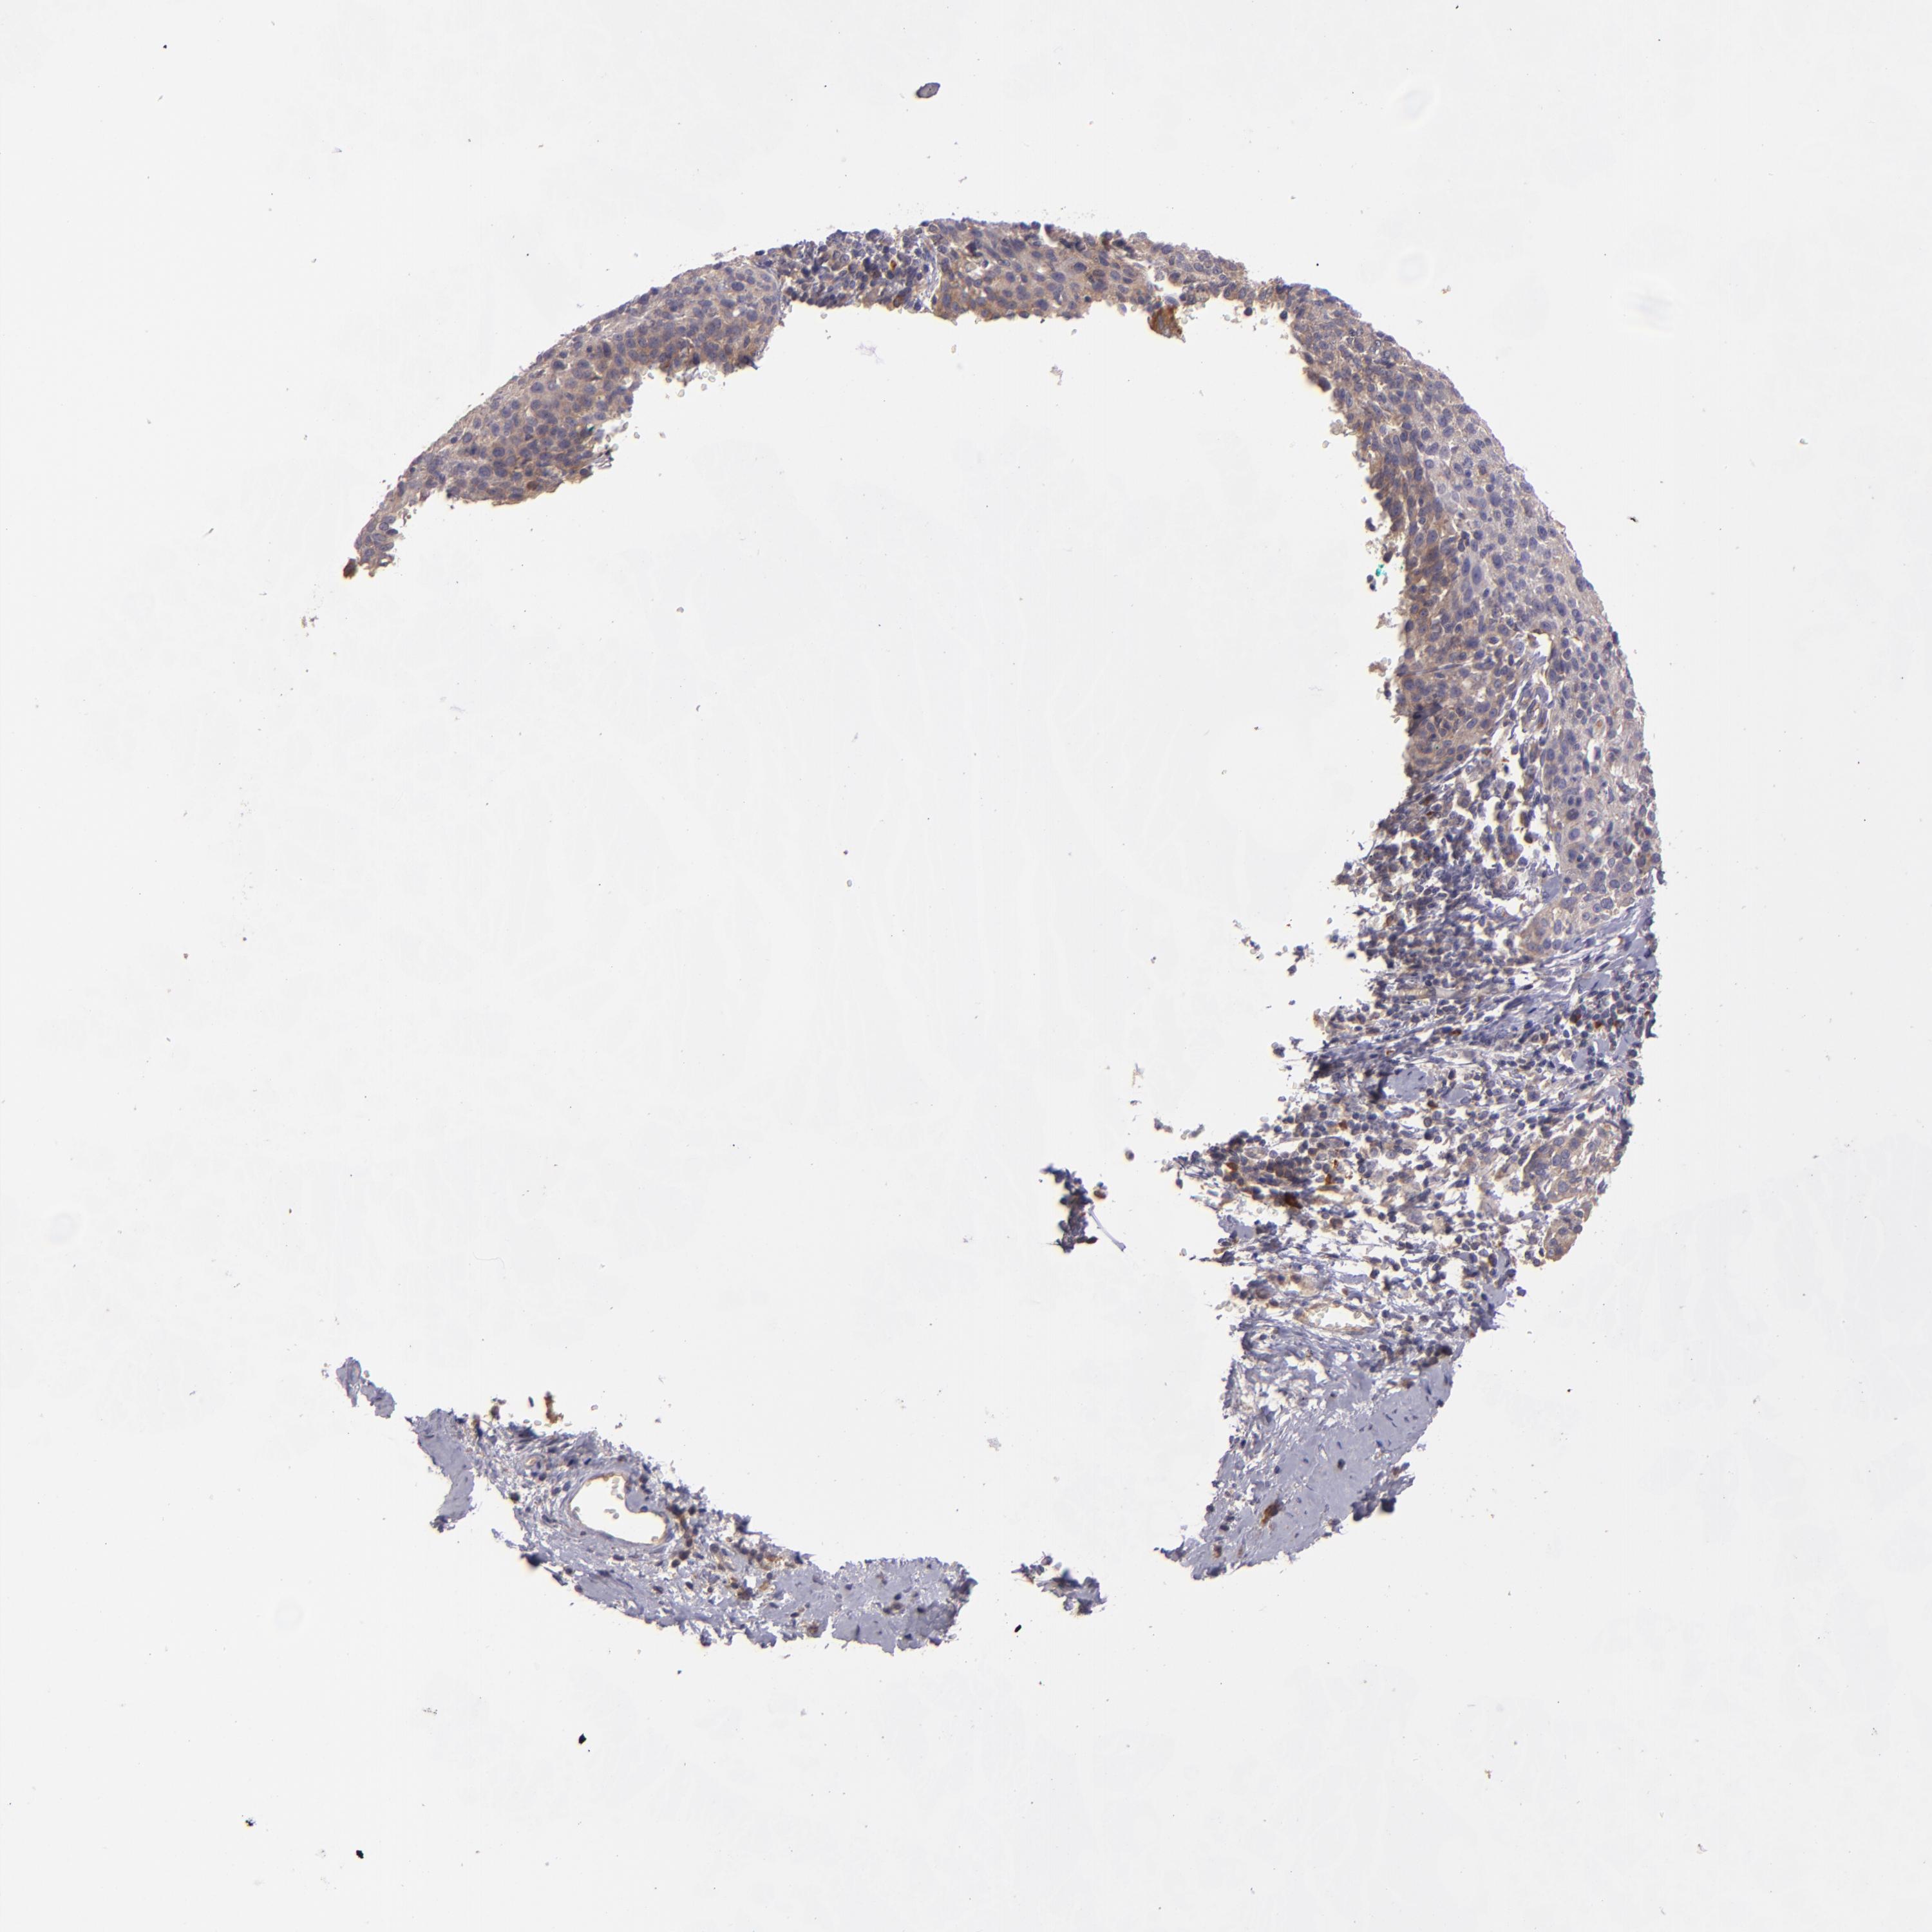

CERVICAL CANCER - Protein expressioni

A mouse-over function shows sample information and annotation data. Click on an image to view it in a full screen mode. Samples can be filtered based on level of antibody staining by selecting one or several of the following categories: high, medium, low and not detected. The assay and annotation is described here.

Note that samples used for immunohistochemistry by the Human Protein Atlas do not correspond to samples in the TCGA dataset.

Antibody stainingi

Antibody staining in the annotated cell types in the current human tissue is reported as not detected, low, medium, or high, based on conventional immunohistochemistry profiling in selected tissues. This score is based on the combination of the staining intensity and fraction of stained cells.

Each image is clickable and will lead to virtual microscopy that enables deeper exploration of all samples and also displays staining intensity scores, fraction scores and subcellular localization as well as patient and tissue information for each sample.

Antibody HPA001490

Antibody HPA013616